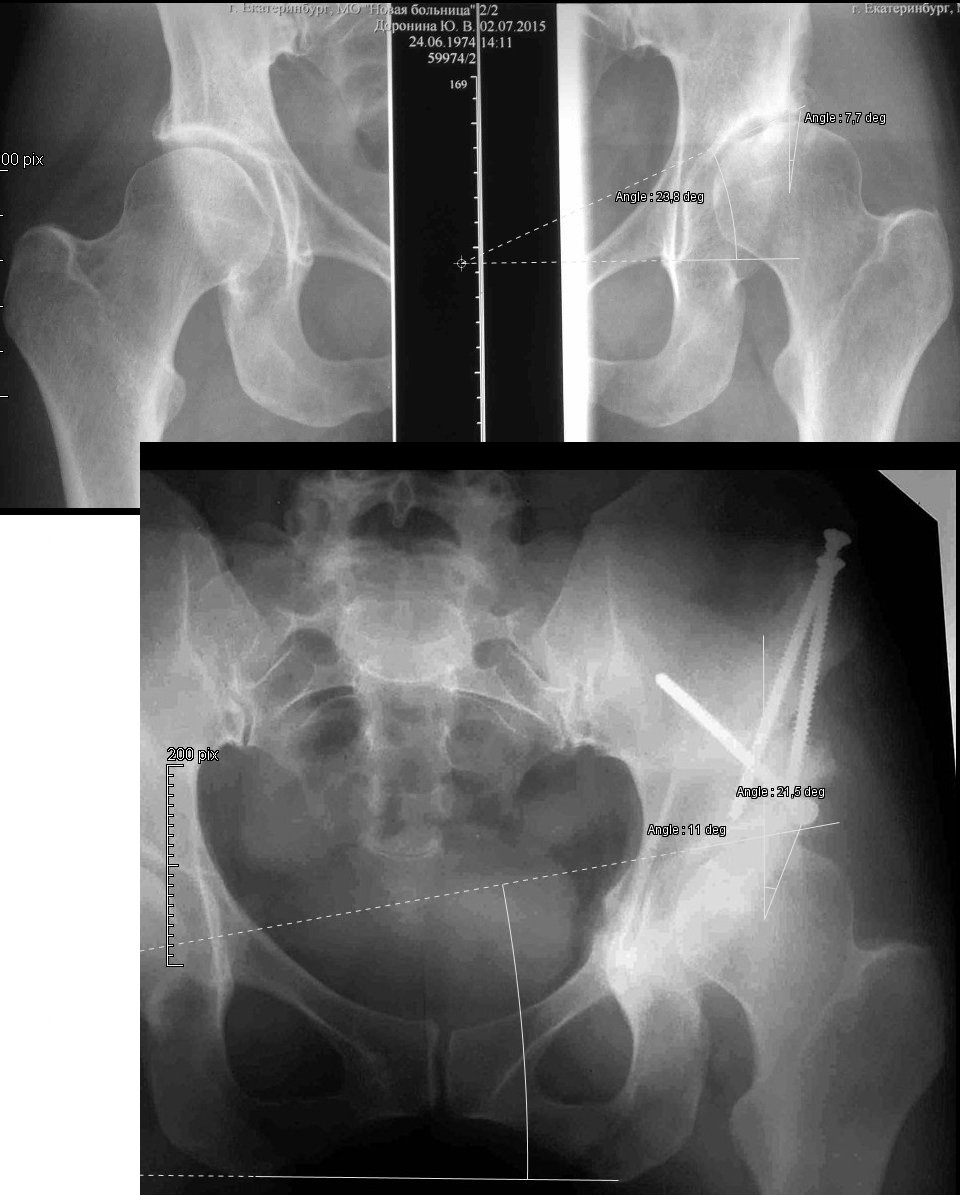

Чтобы определить, что изменилось после операции имеет смысл пользоваться точными измерительными инструментами.

Зная нормальные значения углов, можно понять, насколько в результате операции удалось приблизиться к норме. Согласно моим замерам достигнуты физиологические значения угла Виберга (с 7,7 до 21,5) и наклона опорной поверхности(с 23,8 до 11). Хотя по-хорошему среди предоперационных снимков должна быть тоже обзорная проекция таза. Можно еще мерить процент погружения головки во впадину, индекс глубины впадины и другие индексы. Конечно, значения могут варьировать в разных руках, но так будет хотя бы не "на глаз", можете представить свои измерения и показать на сколько какой параметр изменился.

Успешность предшествовавшей ПАО весьма сомнительна (с позволения ув. Шведовченко Игоря Владимировича добавлю): угол Виберга (или LCEA, если Вам удобнее англоязычность) до операции в лучшем случае 14 градусов, после - 18 градусов по самым позитивным представлениям (при норме 26-35). Угол наклона крыши вертлужной впадины (Tonnis angle): до операции - 20 гр., после 13 гр. (норма 0-10).